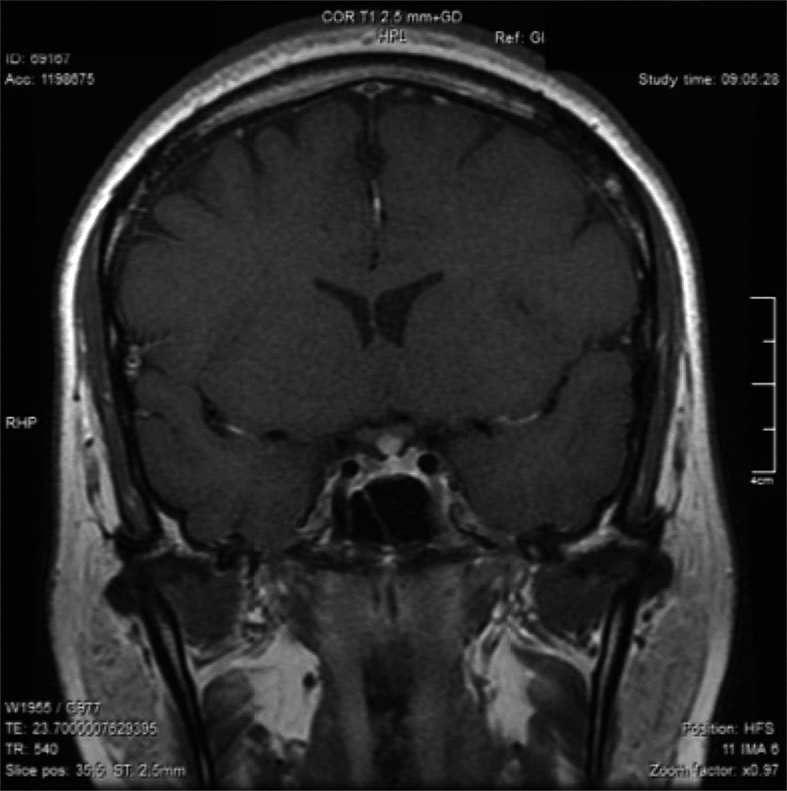

Posteriormente, consultó con especialista endocrinólogo donde se le solicitó exámenes que destacaba: glicemia 97 mg/dl, creatininemia 0,71 mg/dl, sodio 145 mEq/l, potasio 3,6 mEq/l, cloro 105 mEq/l, FSH 3,8 MUI/ml, Estradiol 12 pg/ml, prolactina 20,6 ng/ml, TSH 4,69 UI/ml, T4 libre 1,0 ng/dl, IGF-1 30,8 ng/ml (130-354), cortisol 151 ng/ml (40-230). Resonancia magnética (RM) de la región selar informó “silla turca normal, engrosamiento nodular del tercio medio distal del tallo hipofisiario y no se identifica señal de la neurohipófisis” (Figura 1). Se ajustó DDAVP a 2 puff en la mañana y 1 puff en la tarde, logrando ya normalizar la diuresis diurna y no tener nicturia. Se solicitó control RM en forma precoz para evaluar evolución de engrosamiento del tallo y segunda resonancia informó “no se identifica señal de neurohipófisis, evolución regresiva del engrosamiento del tallo hipofisiario respecto a RM previa” (Figura 2). Se establece diagnóstico de Infundibuloneurohipofisitis, Diabetes Insípida central y amenorrea secundaria por hipogonadismo hipogonadotrópico. La paciente evoluciona en forma adecuada, asintomática, con completo control de la diuresis, y dado el compromiso gonadal y la edad se inició terapia reemplazo hormonal. Siguiente RM evidenció normalización del grosor del tallo hipofisiario, sin evidenciar la neurohipófisis.

Figura 1. Engrosamiento nodular del tercio medio distal del tallo hipofisiario.

Dentro del correcto diagnóstico de la INH está la neuroimagen, donde la RM es el método de elección. Los hallazgos comúnmente encontrados son el engrosamiento del infundíbulo y del tallo hipofisiario (se considera engrosamiento si es mayor a 4 mm) y la pérdida de señal de la neurohipófisis (hay que considerar que el 10% de la población normal no la presenta, especialmente en ancianos). Esta asociación, ausencia de señal de neurohipófisis y engrosamiento del tallo hipofisiario, son altamente sugerentes de INH. En nuestra paciente se encontraron ambos fenómenos, y considerando la regresión del engrosamiento del tallo hipofisiario lo hacía compatible con INH. La adenohipófisis en la RM es usualmente normal en tamaño e intesidad a la señal. Siendo el engrosamiento del tallo hipofisiario el hallazgo cardinal a la imagenología, inicialmente se le denominaba “Stalkitis” a esta entidad10; sin embargo, la denominación INH es la más idónea debido a que anatomopatológicamente el compromiso es del infundíbulo, tallo y neurohipófisis. Respecto al engrosamiento del tallo hipofisiario en muy importante considerar su diagnóstico diferencial9. Una adecuada historia clínica, manifestaciones clínicas, imagenología y en ocasiones biopsia darán el diagnóstico adecuado. En la Tabla 1 se enumeran las etiologías de engrosamientos del tallo hipofisiario aisladas.